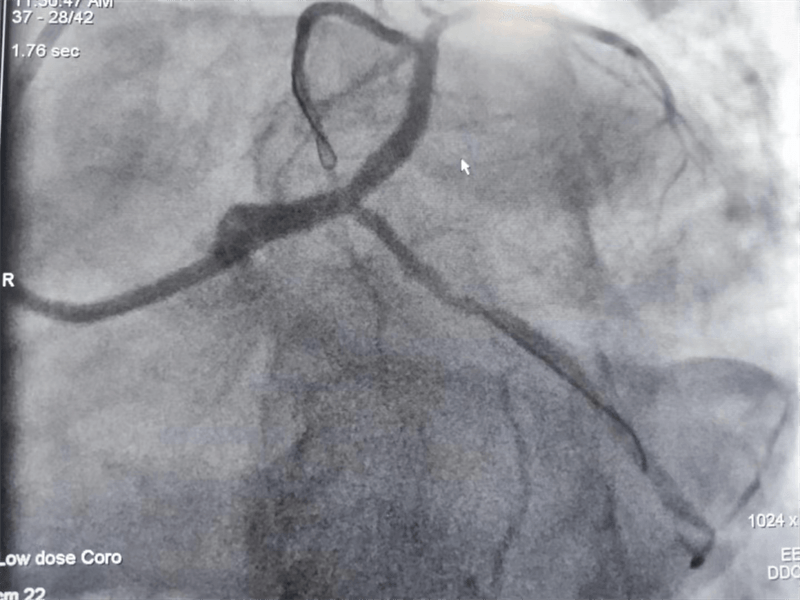

63岁的张大伯因严重心绞痛住院,心电图可见明显明显心肌缺血。主治医师黄永涛向患者讲明病情后,征得患者和家属同意,行冠脉造影检查。真是不做不知道,一做吓一跳。

冠脉造影结果提示:左主干末端及前降支开口处99%狭窄,回旋支开口处80-90%狭窄,中段支架内100%闭塞。看到造影结果时,在场医护人员无不惊出一身冷汗:左主干病变“细”如发丝——生死一线牵!患者拒绝搭桥手术,所以选择介入处理该病变。